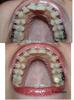

5 месяцев или пол года..)))

Прилагаю коллажи..., На которых как мне казалось, 6 месяцев, но посмотрев здесь, поняла что ошиблась на месяц...)) На фото нам 5 месяцев)))